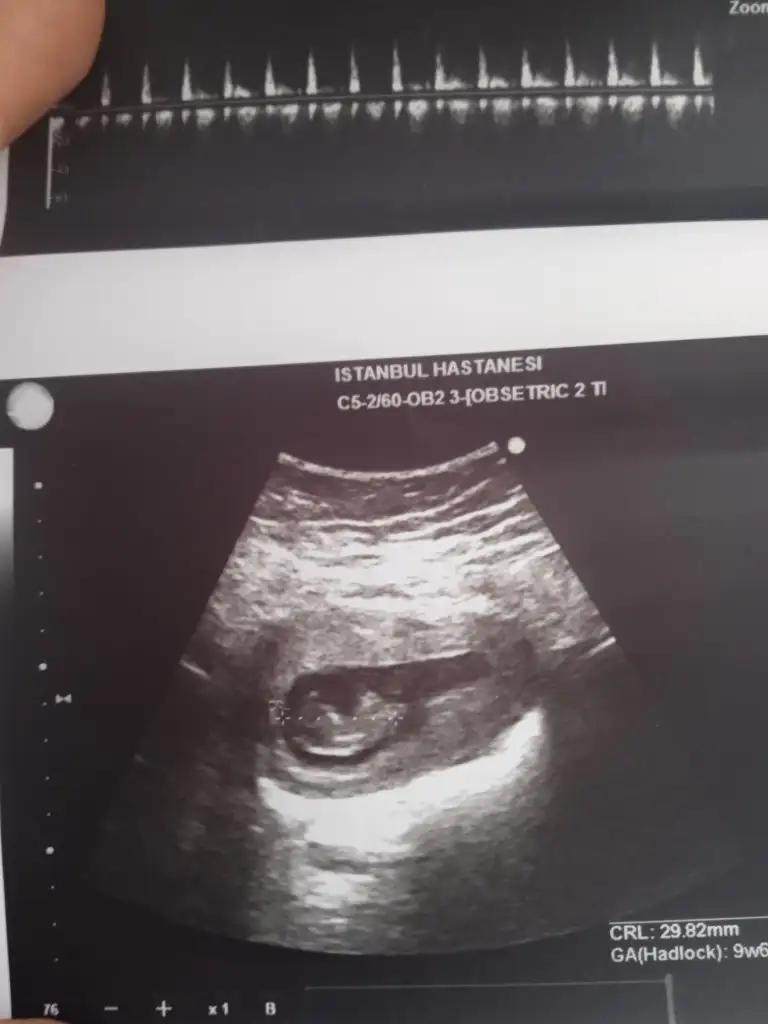

Ben de bakar bakmaz ağa gibi uzanmış bir adam gördüm, ama tamamen totomdan sallıyorumCinsiyet tahmini yapabilir misiniz nolur lütfen ?

Teşekkür ediyorum nereden anladınız acaba ?

Oglum ve kizimda ki ultrason görüntüsünden.Teşekkür ediyorum nereden anladınız acaba ?

Oglum fotodaki gibiydi.

Kızımda göbek kısmı cok şişikti.